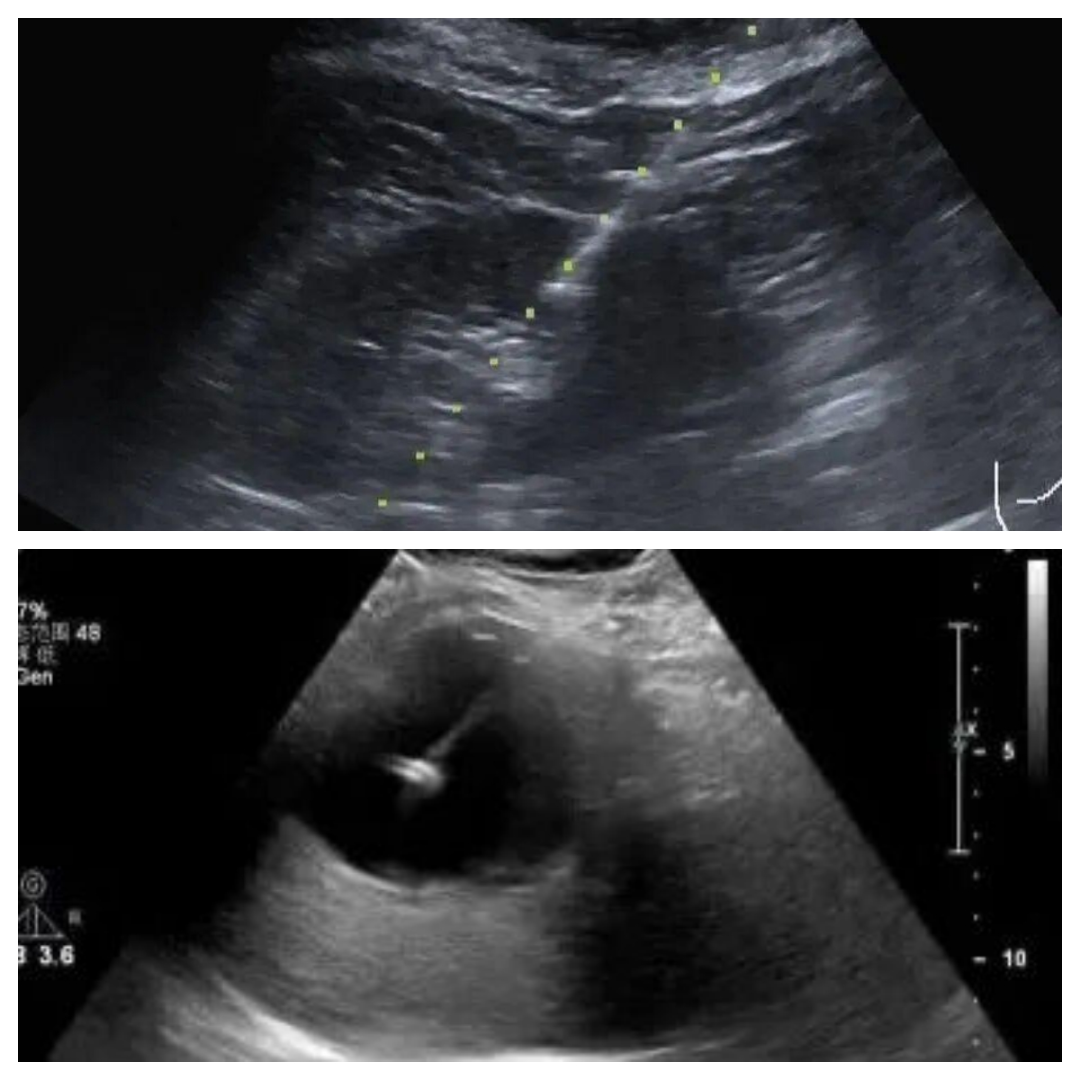

过程:超声实时引导下,将活检针精确刺入结节,取出几条“小米粒”大小的组织送病理检查,是诊断的“金标准”。

屏幕上实时显示针尖的完整进针路径,确保绝对精准,避开大血管和重要脏器,安全高效。